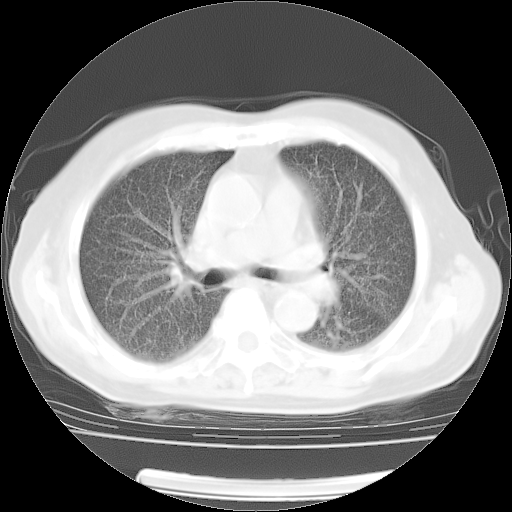

肺部CT平扫未见异常。